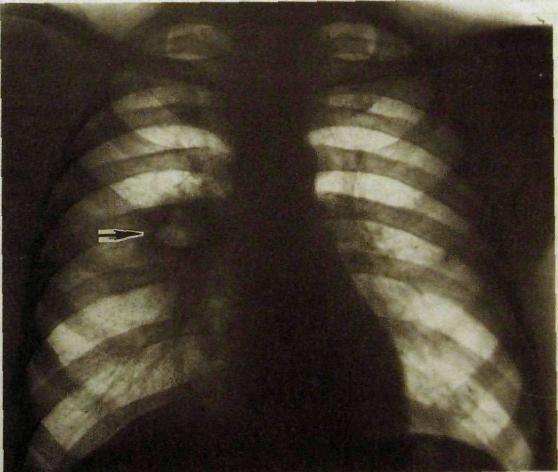

Рентгенодиагностика бронхопневмонии: Советы и примеры

Раздел: Альбом открытий